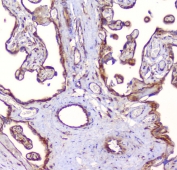

IHC staining of FFPE human placenta with RP2 antibody at 1ug/ml. HIER: boil tissue sections in pH6, 10mM citrate buffer, for 10-20 min followed by cooling at RT for 20 min.